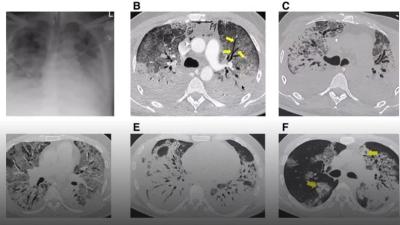

इस फोटो में एक्स-रे को अलग तरह से देखा जाता है। जिसमें कोरोना वायरस के घाव पूरी तरह से दिखाई दे रहे हैं। सीटी स्कैन रिपोर्ट दाएं और बाएं ओर के फेफड़े को अलग-अलग वर्गों में विभाजित करती है और कई अंक देती है।

यदि स्कोर पांच है तो इसे हल्का माना जाता है और यदि यह 20 से ऊपर है तो स्थिति गंभीर है। इस प्रकार, कम से कम पांच से सात दिनों के बाद सीटी स्कैन द्वारा कोरोना वायरस का पता लगाया जा सकता है।